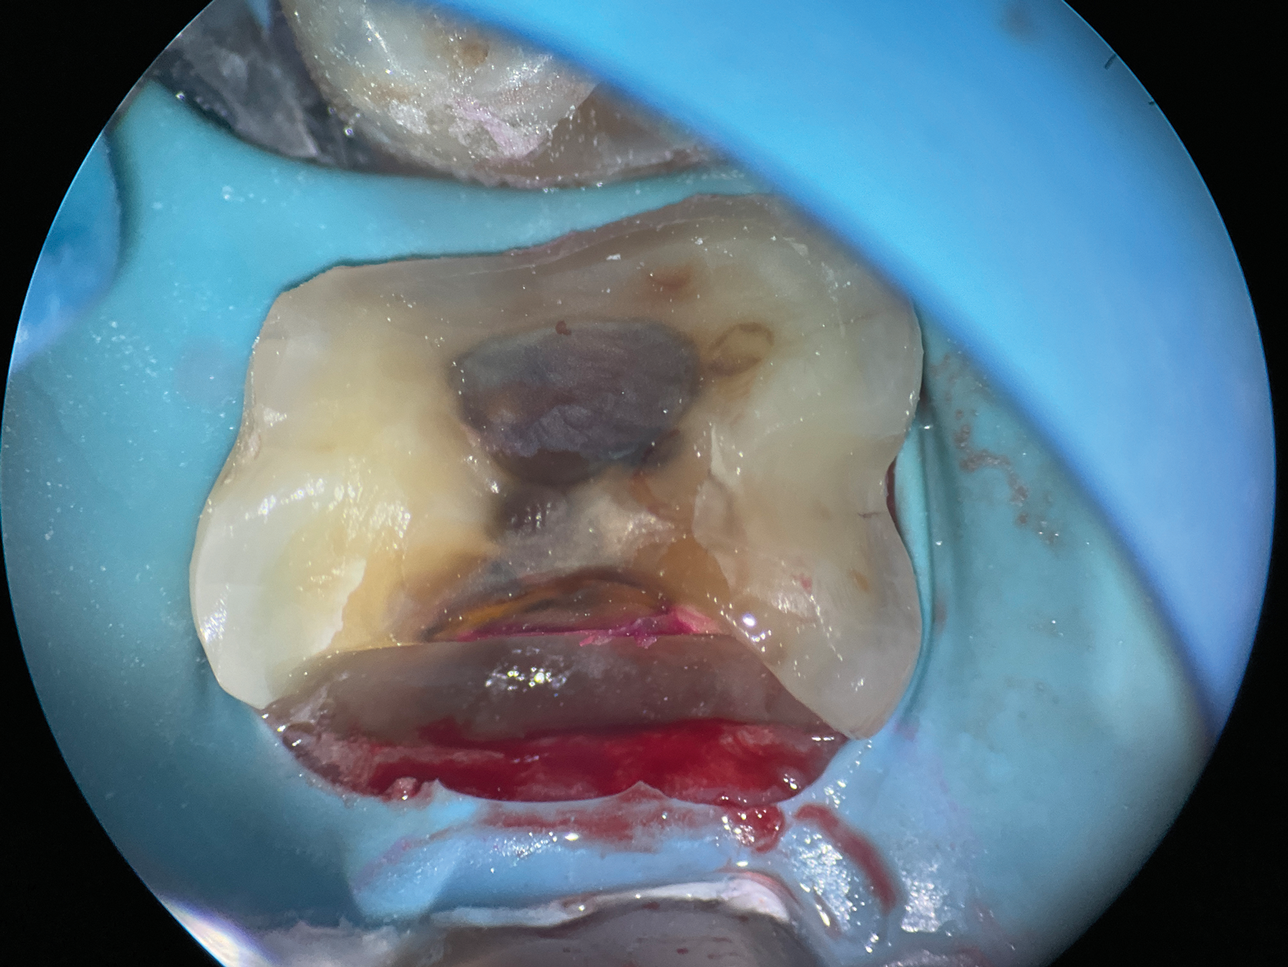

Extremely Deep Defects: Assisting Absolute Seal

In cases involving extremely deep defects that extend to the bone level, achieving an adequate seal and proper isolation for adhesive procedures can be particularly challenging (Figure 10 and Figure 11). Oftentimes, a single matrix proves insufficient to reach the depth of such defects and effectively shield the cavity from contamination by saliva or blood (Figure 12).

(10.) A close-up distolingual view of a mandibular molar after the removal of caries that extended to the bone level.

Figure 10

(11.) A Willems probe was used to determine that the depth of the margin was approximately 7 mm from the occlusal surface.

Figure 11